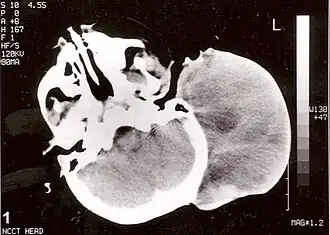

![]() Tomografía axial computarizada sin contraste de la cabeza, que muestra una gran masa sin extensión intracraneal. El diagnóstico fue de rabdomiosarcoma alveolar congénita post auricular. | ||